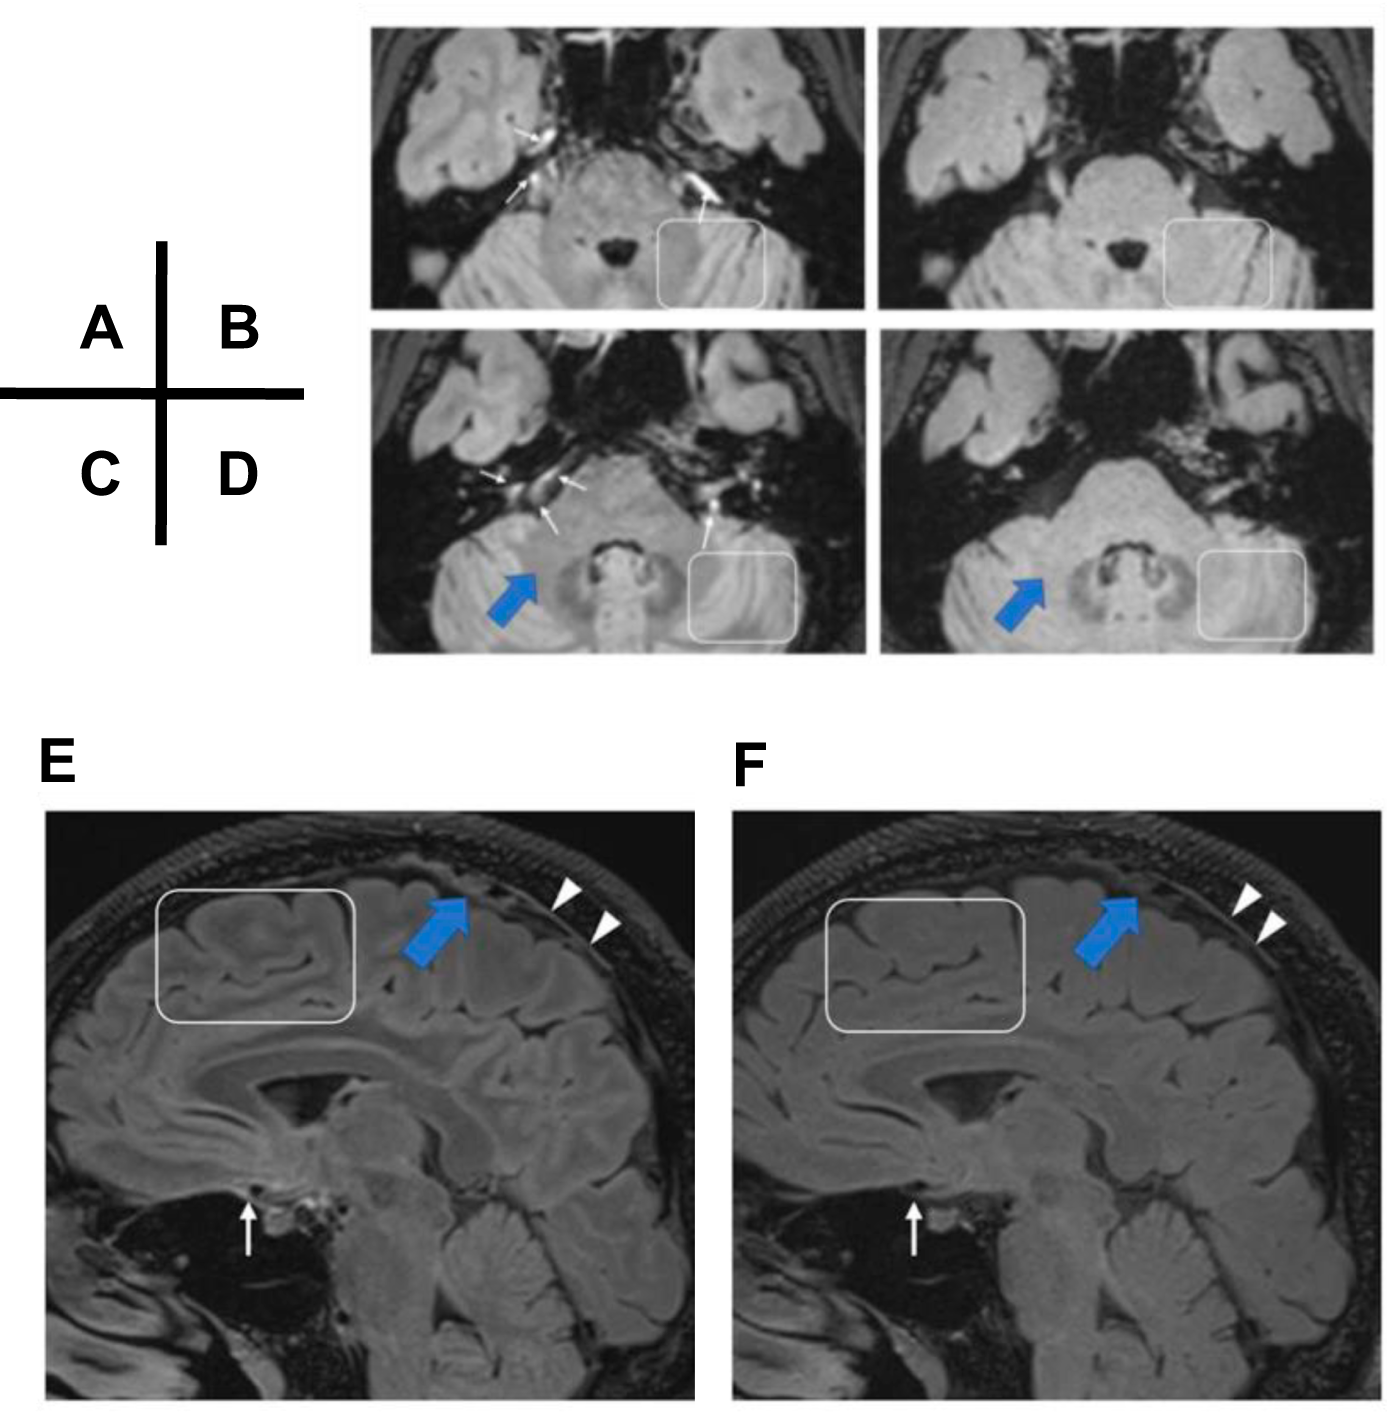

Fig. 1: Ventral and dorsal lymphatic/ISF signal differences between the T2-selective IR and conventional IR.

Lymphatic fluid/ISF signals in the ventral and dorsal regions are similarly visible in images obtained with T2-selective IR (A, C, E), but not in images obtained with the conventional inversion pulse in the study’s volunteer case (B, D, F). The ventral signal (white arrows) and dorsal signal (white arrowheads) cannot be seen in conventional IR series. The entire parenchyma, including gray matter, white matter, and middle cerebellar peduncles, present with similar signal intensity with the conventional IR technique (B, D, F), whereas these structures can be seen clearly with T2-selective IR sequences (A, C, E) (white boxes and blue arrows). (Adapted from Figs. 1 and 2 of Naganawa et al., Nat Commun. submitted)2.